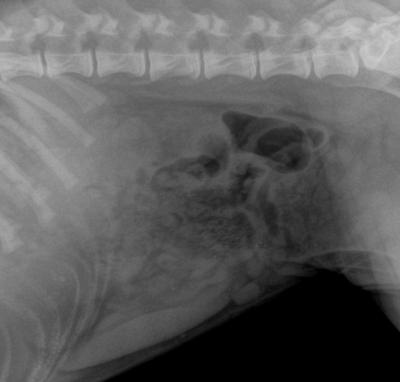

Toto štěně rhodéského ridgebacka začalo být z ničeho nic apatické. RTG dutiny břišní odhalilo neznámé těleso v dutině břišní.

Toto je rentgen dutiny břišní 4 kg maltézského psíka. Cizí těleso jsme podle rtg snímku nedokázali identifikovat.